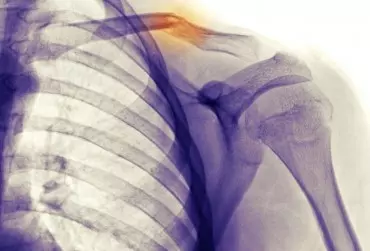

Postępowanie fizjoterapeutyczne po złamaniu obojczyka

Złamania obojczyka stanowią ok. 2–5% wszystkich złamań oraz ok. 40–60% wszystkich złamań w okolicy obręczy barkowej. Większość obrażeń obojczyka występuje na skutek bezpośredniego urazu okolicy barku.